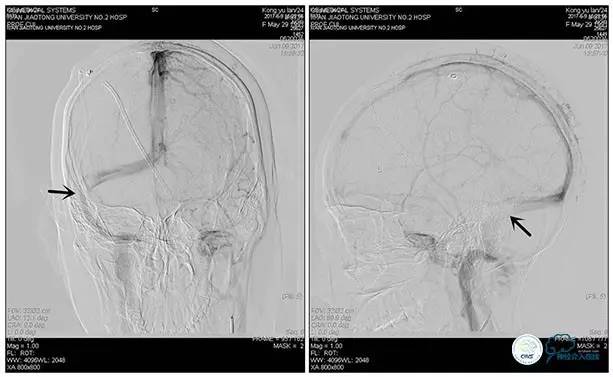

术中右侧ICA造影

右侧ICA斜位及窦内造影

右侧ICA斜位

窦内造影及路图

术中测压:

远端:520mmH2O,

近端:190mmH2O。

术后右侧ICA造影

术后远、近端压力差为:0

术后右侧ICA斜位